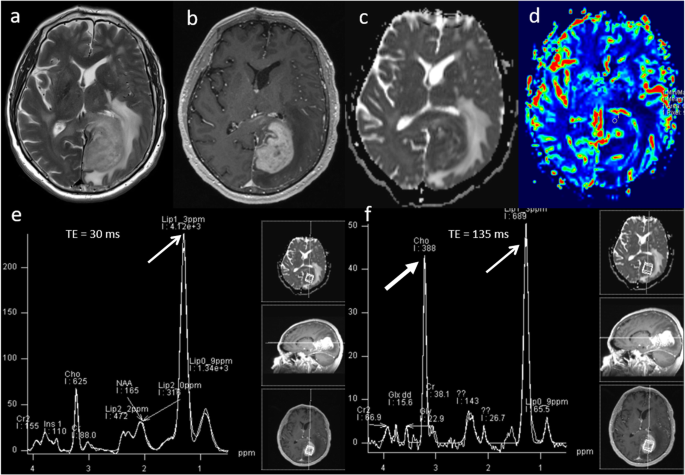

Primary central nervous system lymphoma (PCNSL) is a form of extranodal non-Hodgkin’s lymphoma and unlike other brain neoplasms, resection of PCNSL rarely provides benefit, instead chemotherapy and radiotherapy are preferred treatment choices [16]. Hence, it is important to differentiate lymphoma from high-grade glioma. Conventional imaging appearances for PCNSL are an avidly homogenously enhancing mass, which is T1 hypointense and T2 iso- to hypointense. There is little mass effect for size and limited surrounding vasogenic oedema. Multiparametric MRI in PCNSL demonstrates a very low ADC suggesting dense cellular packing, lower perfusion due to lack of angiogenesis, very high Cho/Cr ratio due to high membrane turnover, high lipid peak at 1.3 ppm due to infiltration by macrophages even without necrosis [17] and very low NAA levels [18]. Imaging features of typical PCNSL is demonstrated in Fig. 2. However, it is important to note that PCNSL in immunocompromised patients may be more heterogeneous, with central necrosis and haemorrhage.

Lymphoma. Conventional MRI Findings: a, b Axial T2W and post-contrast T1W sequences show a large homogenously enhancing lesion in the left occipital lobe. c ADC map shows very low ADC (< 600 × 10−6 mm2 s−1) throughout the lesion. d PWI shows low perfusion throughout the lesion compared to normal-appearing contralateral white matter. e, f MRS shows very high Cho/Cr ratio (> 6, thick arrow) and very high lipid peaks in a non-necrotic appearing lesion (TE 30 ms and 135 ms, thin arrows). The low perfusion, very low ADC, very high lipid peak in a non-necrotic appearing lesion and high choline peak are characteristic of lymphoma. Histopathology confirmed a diffuse large B cell PCNSL